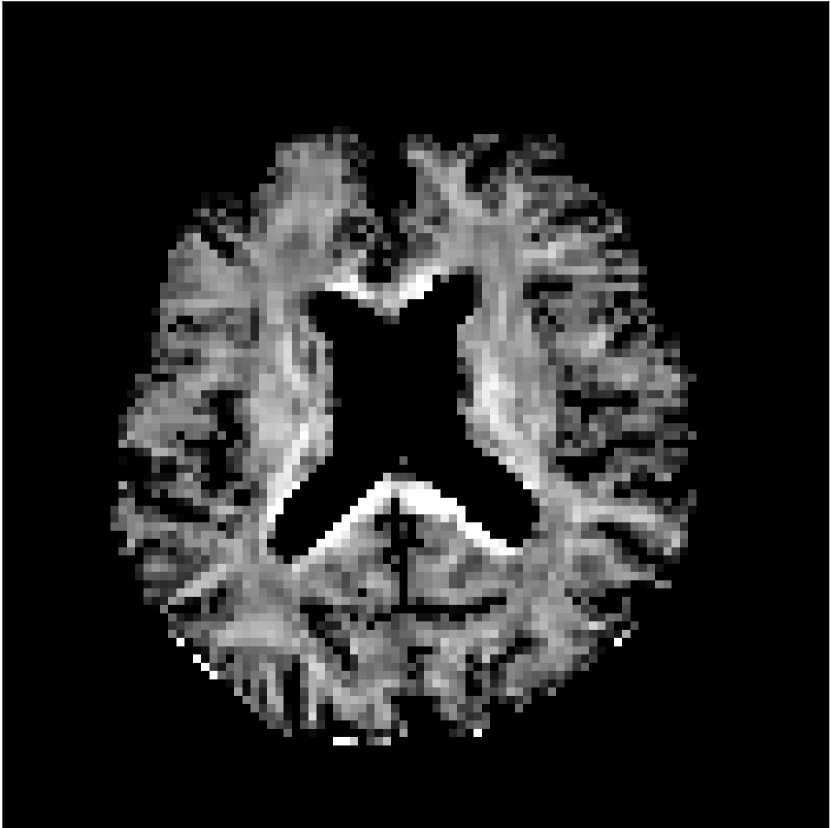

Figure 8 shows examples of non-diffusion-weighted images before and after processing. The raw images (Raw) served as the input for the magnitude deep learning (MCNN) and complex deep learning (CCNN) methods.

Raw 𝐱tsubscript𝐱𝑡\mathbf{x}_{t}

MCNN, fθ^(𝐱t)subscript𝑓^𝜃subscript𝐱𝑡f_{\hat{\theta}}\left(\mathbf{x}_{t}\right)

MCNN Resid., Ric(𝐱t)fθ^(𝐱t)Ricsubscript𝐱𝑡subscript𝑓^𝜃subscript𝐱𝑡\text{Ric}(\mathbf{x}_{t})-f_{\hat{\theta}}\left(\mathbf{x}_{t}\right)

CCNN, fθ^(𝐱t)subscript𝑓^𝜃subscript𝐱𝑡f_{\hat{\theta}}\left(\mathbf{x}_{t}\right)

CCNN Resid., Ric(𝐱t)fθ^(𝐱t)Ricsubscript𝐱𝑡subscript𝑓^𝜃subscript𝐱𝑡\text{Ric}(\mathbf{x}_{t})-f_{\hat{\theta}}\left(\mathbf{x}_{t}\right)

No PF

5/8 PF

Figure 8: Examples of non-diffusion-weighted images from in vivo data at b=0𝑏0b=0 s/mm2. Artifacts in the Raw image, 𝐱tsubscript𝐱𝑡\mathbf{x}_{t}, are corrected by the MCNN and CCNN models, fθ^(𝐱t)subscript𝑓^𝜃subscript𝐱𝑡f_{\hat{\theta}}(\mathbf{x}_{t}). Also shown are the residuals between the CNN corrections and the original Raw image with Rician bias correction Ric(𝐱t)Ricsubscript𝐱𝑡\text{Ric}(\mathbf{x}_{t}) [10]. The Gibbs artifacts removed by the methods are observed in the residuals. The MCNN method introduces some banding artifacts at the PF 5/8ths factor that are not present in the CCNN method.

Both methods remove artifacts, but the MCNN method allows residual rippling artifacts to pass through in the presence of partial Fourier. These rippling artifacts are not present in the CCNN method.